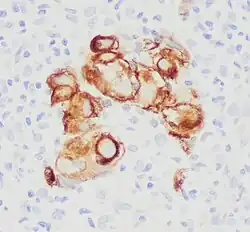

Immunohistochemistry for CK7 of a metastatic undifferentiated carcinoma to a lymph node.

Because the keratin-7 antigen is found in both healthy and neoplastic cells, antibodies to CK7 can be used in immunohistochemistry to distinguish ovarian and transitional cell carcinomas (staining positive) from colonic and prostate cancers (negative), respectively. It is commonly used together with CK20 when making such diagnoses.[8]